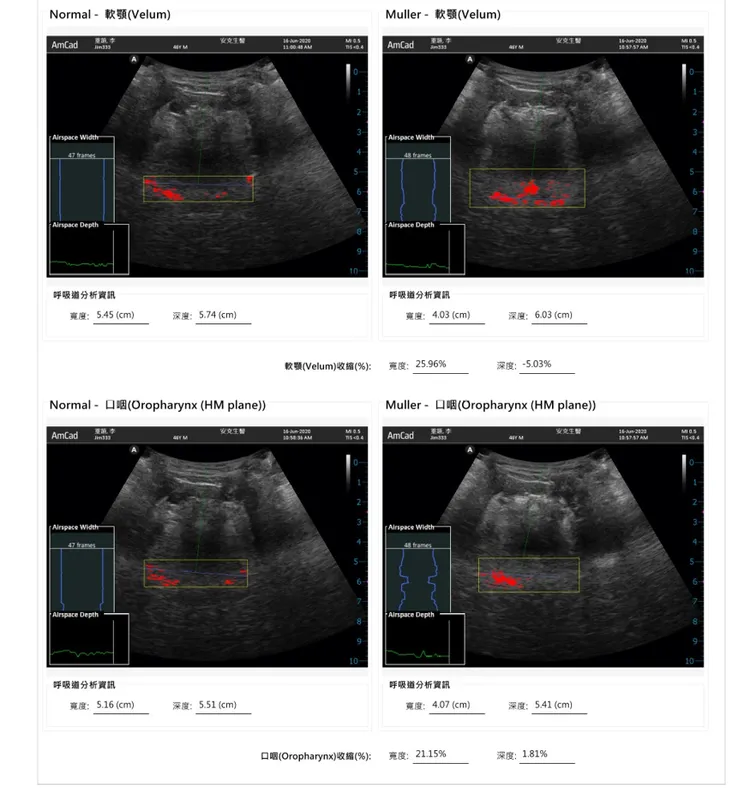

「AI上呼吸道檢測儀」以超音波掃描,並運用AI分析病兆位置。中國附醫提供

為了免除民眾對於侵入式檢查呼吸道組織的擔憂,以及省去睡眠多項生理檢查,杭良文帶領專家團隊,研發「AI上呼吸道檢測儀」,以超音波掃描上呼吸道內組織,檢查軟顎、口咽、舌底、會厭軟骨,在正常呼吸和深吸氣憋住之後的型態與位置變化,以AI大數據輔助分析,預測上呼吸道組織是否塌陷,準確率高達89%,避開麻醉風險。

杭良文強調,「AI上呼吸道檢測儀」結合AI智慧醫療,快速診斷阻塞型睡眠呼吸中止症,上呼吸道的相關檢查,無侵入性、無輻射風險,只需10到15分鐘即可得知上呼吸道變化,若能早期診斷早期治療,可大幅降低心血管疾病及醫療費用。